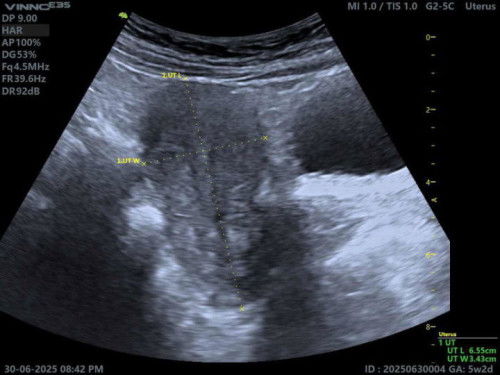

*UPDATE! Terima kasih atas advice mommies semua. Saya dah pergi klinik tadi, Dr kata chemical pregnancy, sebab masih terlalu awal, baru masuk 5 minggu, kantung pun belum sempat terbentuk lagi. Jadi dia akan keluar macam period biasa. Lepastu boleh terus cuba untuk pregnant lagi macam biasa, tak perlu jarak beberapa minggu. Yang penting rahim semua ok, tenang sikit hati ni bila dah jumpa Dr. Hehe Doakan bulan depan saya pregnant lagi ya. Teringin baby girl, sebab first born, dapat boy 🤭 _____ Hello mommies, selama ni period saya teratur. Saya dah delay 7 hari period, masa hari ke-6 delay period masih keluar result pregnant 1-2weeks, tapi masuk hari ke-7 delay period, mula keluar darah banyak macam normal period. Kalau ikut kiraan dari first day period, ikutkan dah masuk 5weeks. Ini kira chemical pregnancy kan? Perlu ke saya jumpa Dr juga untuk check? Atau darah tu akan keluar je macam period biasa, jadi saya tak perlu ke Dr untuk scan? #Needadvice